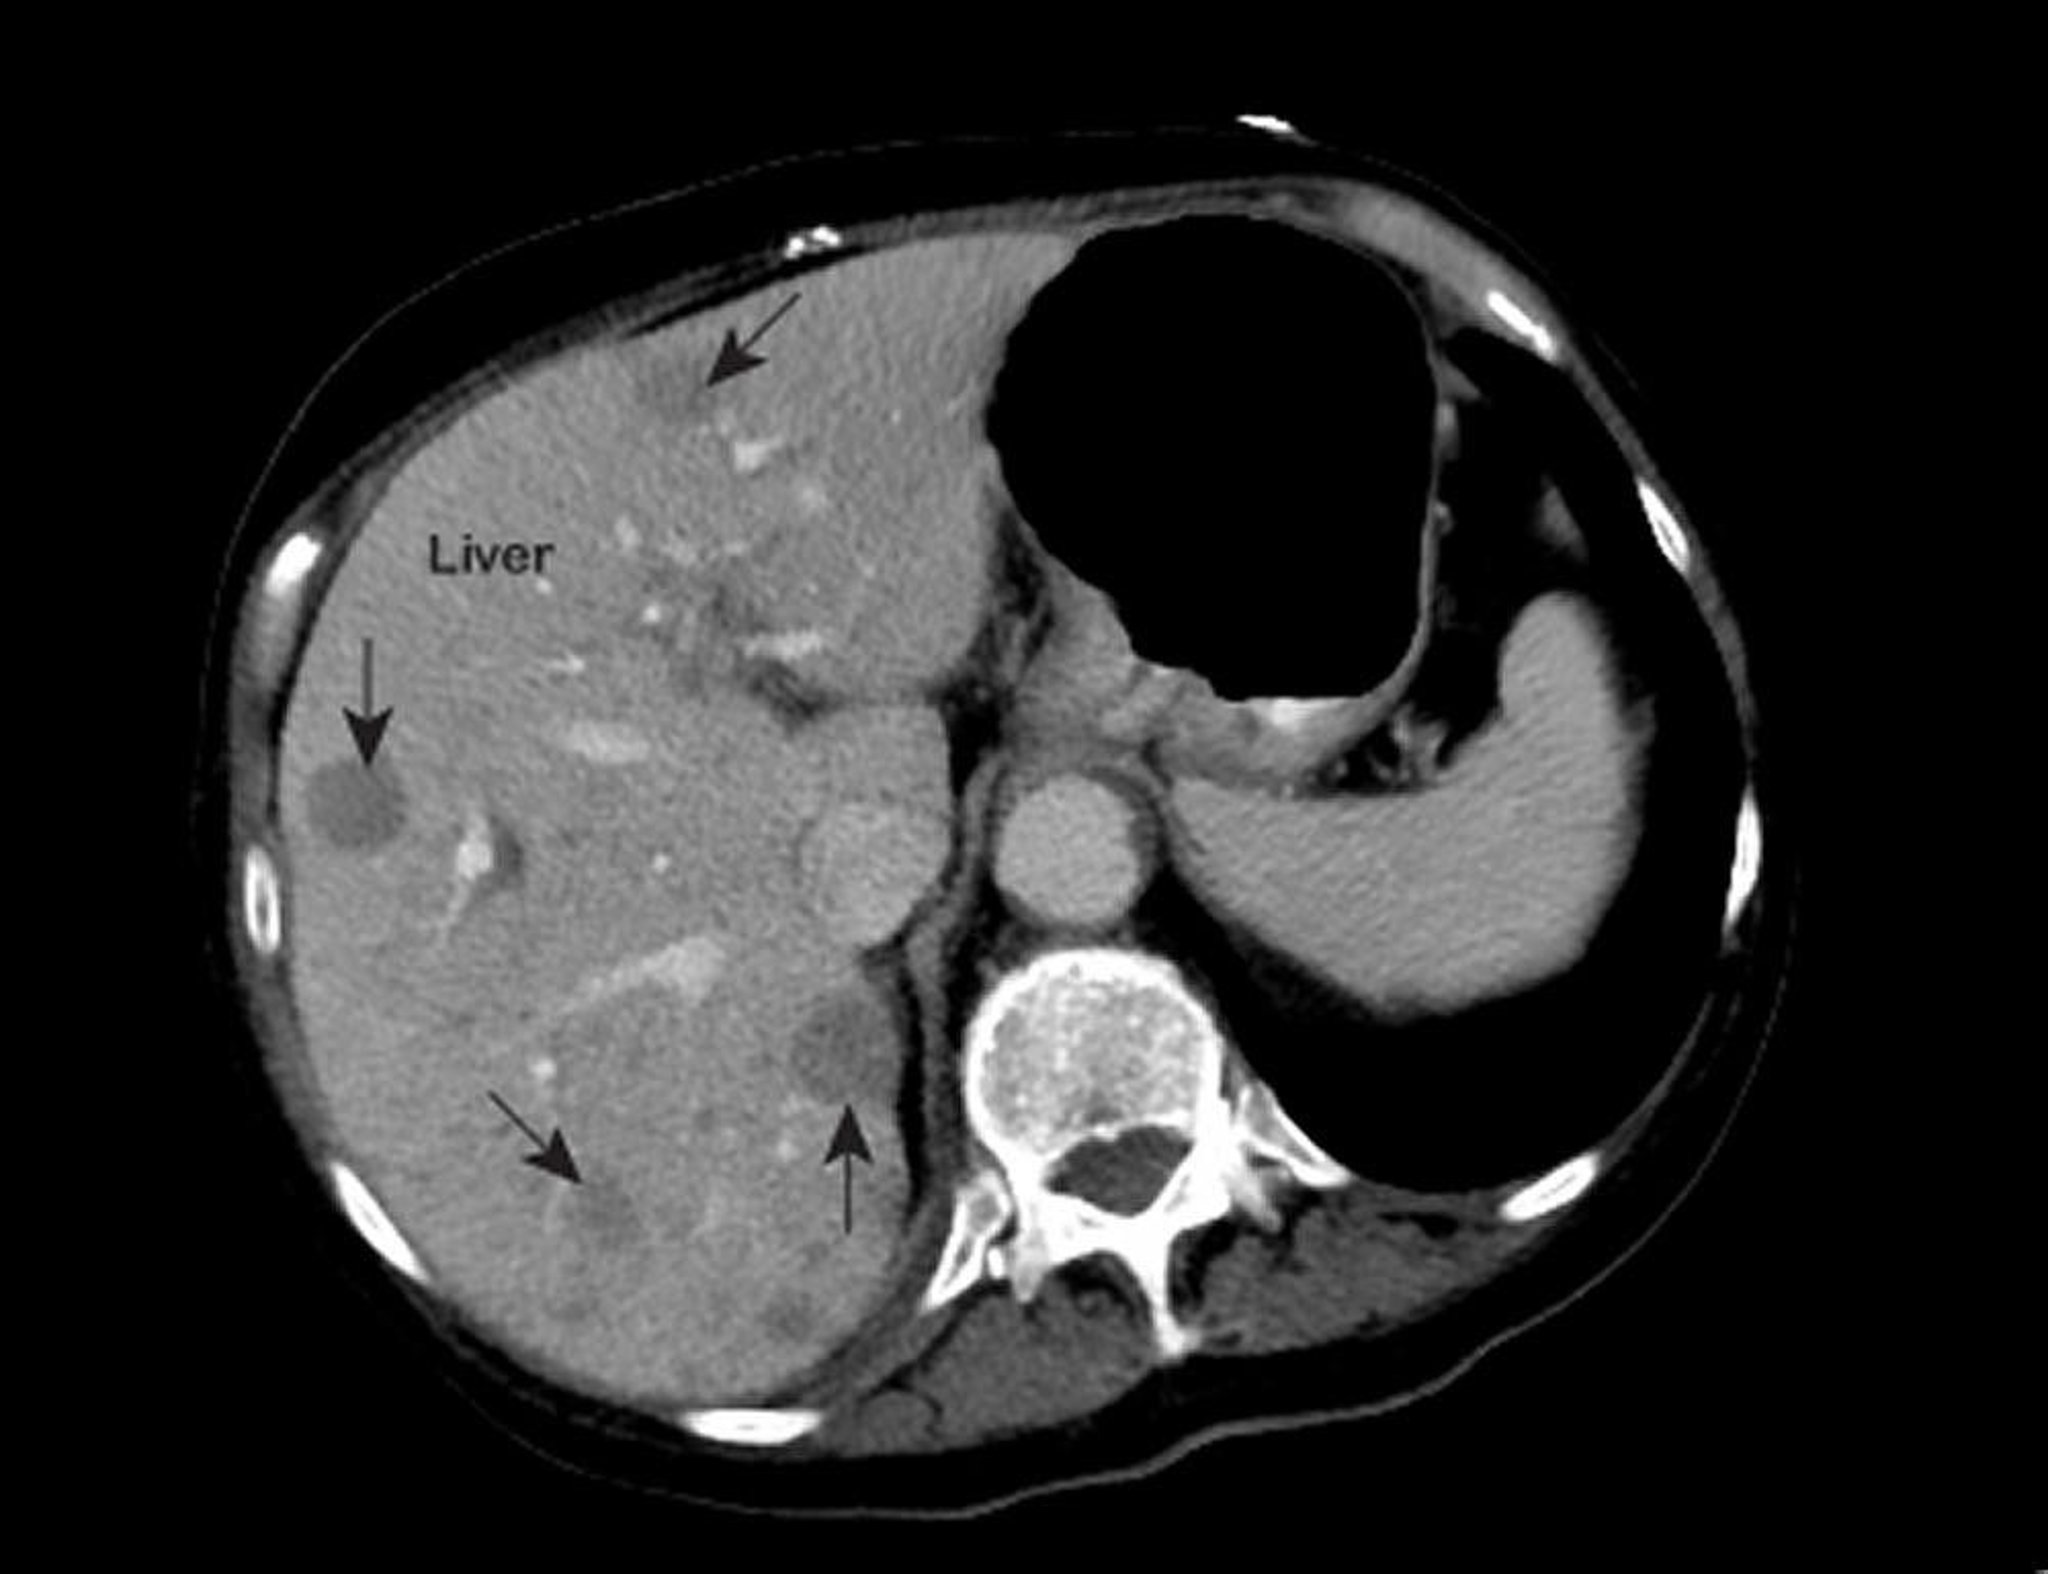

Kanker Hati Metastatik

Hasil pencitraan resonansi magnetik (MRI) dada yang tidak normal menunjukkan area yang tidak normal (ditandai dengan panah) di dalam hati. Temuan ini merupakan ciri khas kanker hati metastatik.

Foto milik Patrick O’Kane, MD.